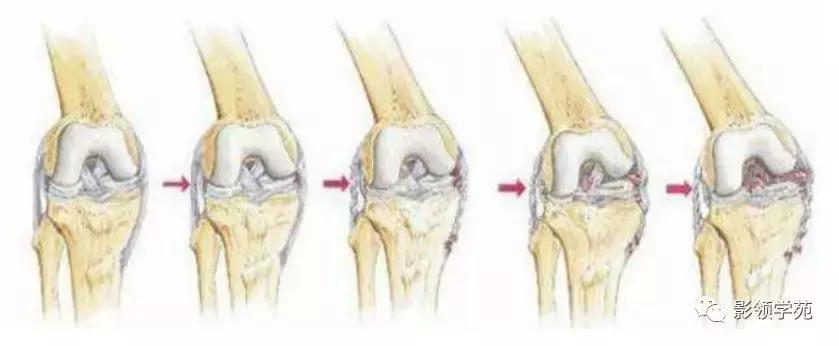

13、韧带损伤

侧副韧带损伤

- 内侧副韧带损伤

- 外侧副韧带(外侧韧带复合体)损伤

交叉韧带损伤

- 前交叉韧带损伤

- 后交叉韧带损伤

韧带的复合损伤